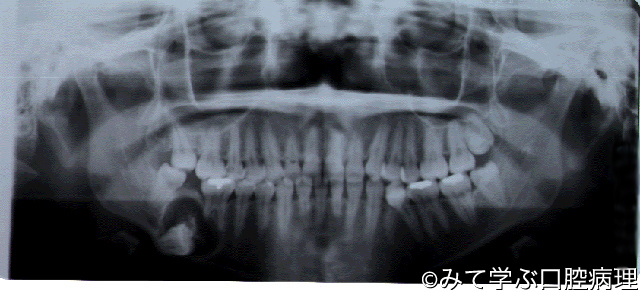

石灰化上皮性歯原性腫瘍

下顎右側第一大臼歯根尖部に埋伏歯を伴った単房性の骨溶解像を認める

埋伏歯の歯冠周囲に綿花状の不透過像がみえる

右下6遠心根にKnife edge状の歯根吸収がみえる